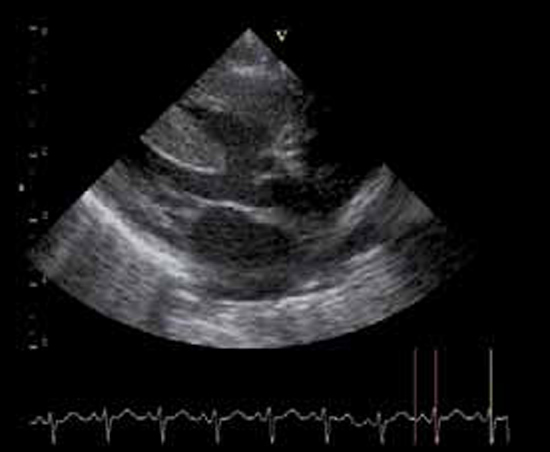

Cardiopathies avec insuffisance cardiaque

La coarctation préductale (c’est-à-dire située en amont de l’émergence du canal artériel ou ductus arteriosus), ou sténose de l’isthme de l’aorte, est une forme grave de la coarctation aortique, symptomatique dès les premiers jours de vie, mais les symptômes n’apparaissent qu’au moment de la fermeture du canal artériel. La chirurgie est urgente (figures 1 et 2).